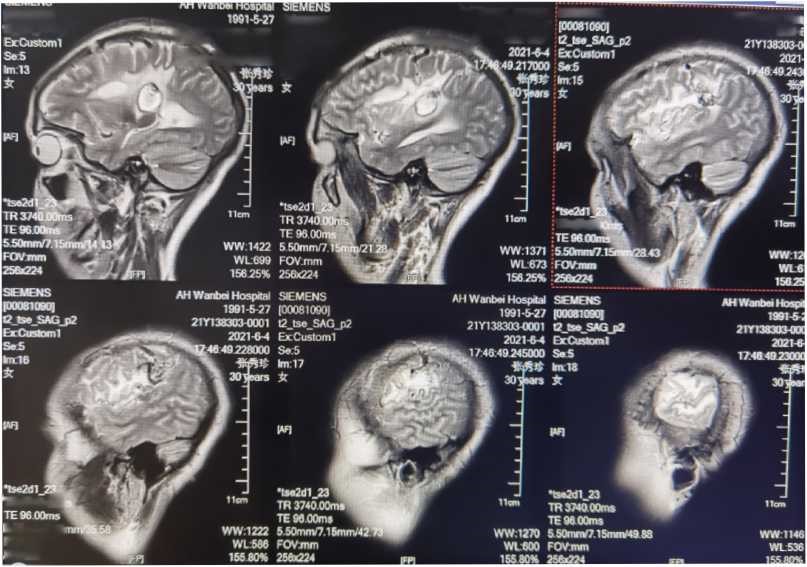

病情稳定后行MRI检查

可以见血管流空影,AVM